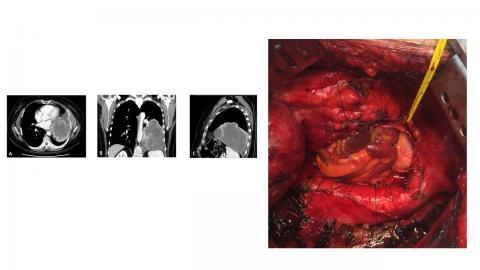

Thoracic surgical oncology

Chest wall resection and reconstruction

ECMO for pulmonary/mediastinal resections